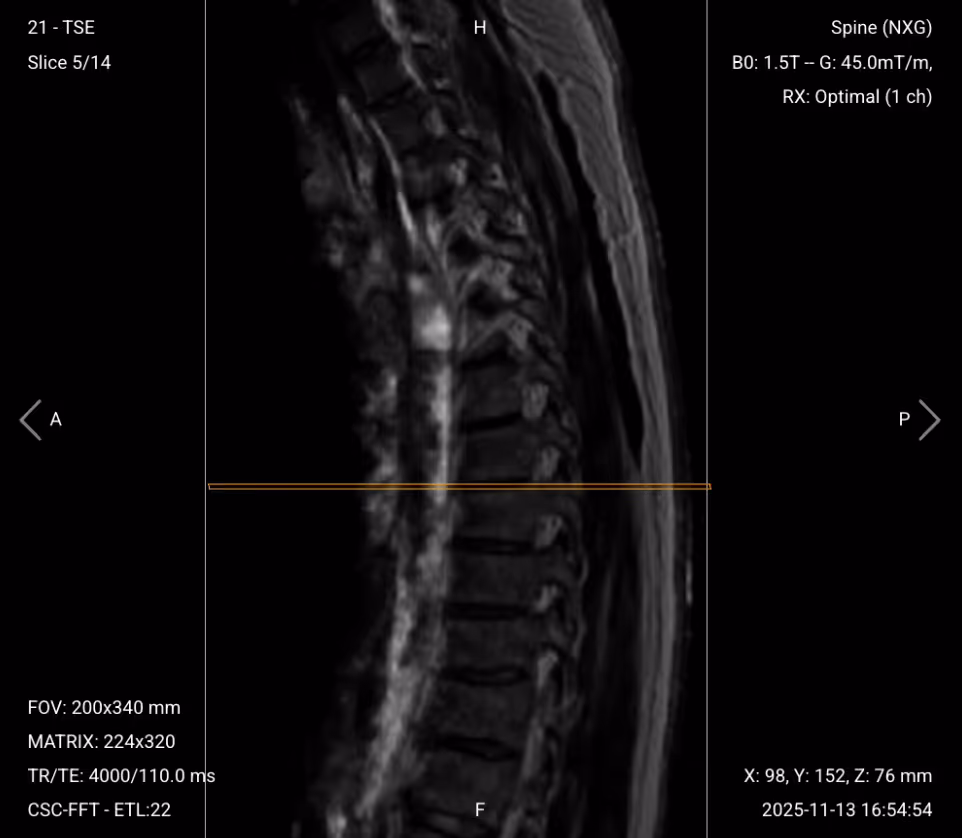

STIR (Short Tau/TI Inversion Recovery) suppresses fat signals completely, which makes water-rich tissues stand out even clearer than with normal T2 TSE. This makes STIR ideal for detecting subtle fluid-related conditions like edema, inflammation, and infections, where increased water content would otherwise be obscured by fat.

In the thoracic spine, STIR is particularly useful for identifying bone marrow edema, infections like discitis or abscesses, inflammatory processes, and multiple sclerosis plaques. STIR provides high lesion visibility when water content might not be easily visible on standard T2 sequences.

We acquire STIR in the sagittal view to visualize the entire spine and detect any fluid-related changes across vertebrae or discs.

✅ Sagittal STIR TSE of Thoracic Spine – Correct Image Example:

Things to Look for in Sagittal STIR: